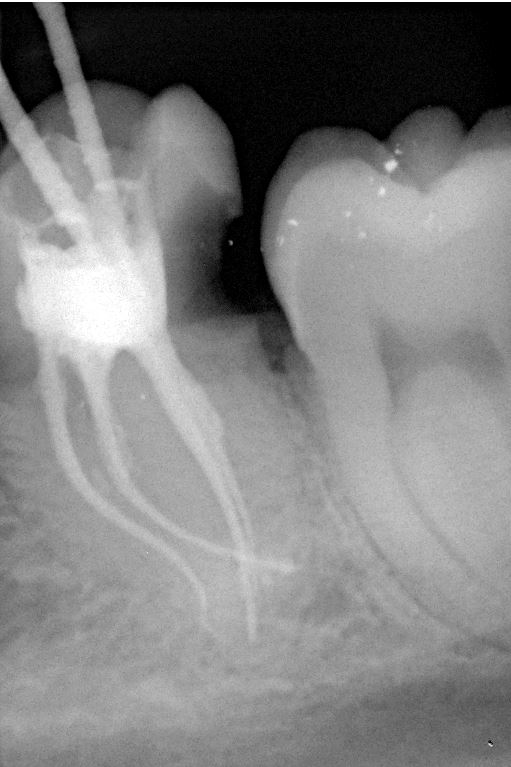

Unter örtlicher Betäubung ist die Behandlung in der Regel schmerzfrei. Nach Entfernung der Karies und nach der Schaffung eines Zugangs in den Zahn werden die Kanaleingänge dargestellt und die Länge jedes einzelnen Kanals wird möglichst exakt unter Anwendung von Röntgen ausgemessen. Abhängig vom zu behandelten Zahn kann die Anzahl der Kanäle stark variieren.

Mit Hilfe der elektronischen Längenmessung und digitalen Röntgenbildern können die Länge und Krümmung der Kanäle bestimmt und der Verlauf beurteilt werden.

Da die Wurzelkanäle sehr klein sind und sich oft verzweigen, ist es nicht immer einfach, alle Kanäle mit ihren Seitenästen aufzufinden.

Nur wenn das Wurzelkanalsystem komplett aufgefunden und gereinigt wird, hat eine Wurzelkanalfüllung eine gute Langzeitprognose.